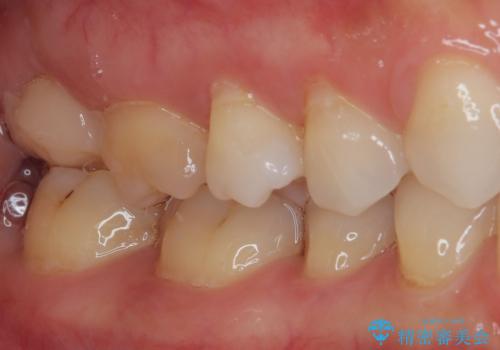

- 上顎大臼歯が食事の度に痛みを感じるとのことで来院された患者様です。

レントゲン写真などで診査を行ったところ、神経組織が壊死し、根尖部周辺の骨に炎症が認められました。

まずは根管治療を行い、症状が消退したことを確認してオールセラミッククラウンにて補綴治療を行うこととしました。